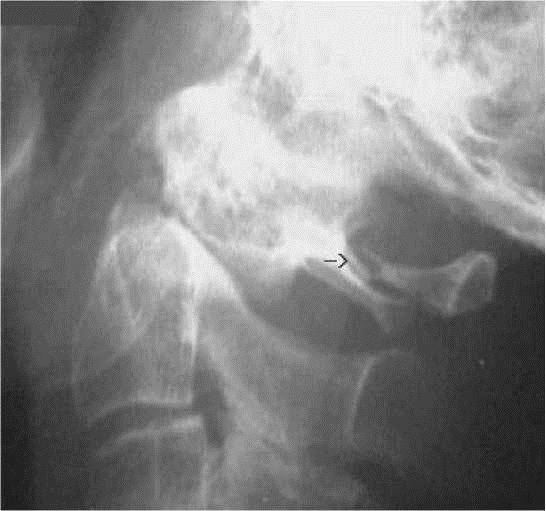

C1/C2 BOUCHE OUVERTE

– – Il est centré au raz des incisives supérieures